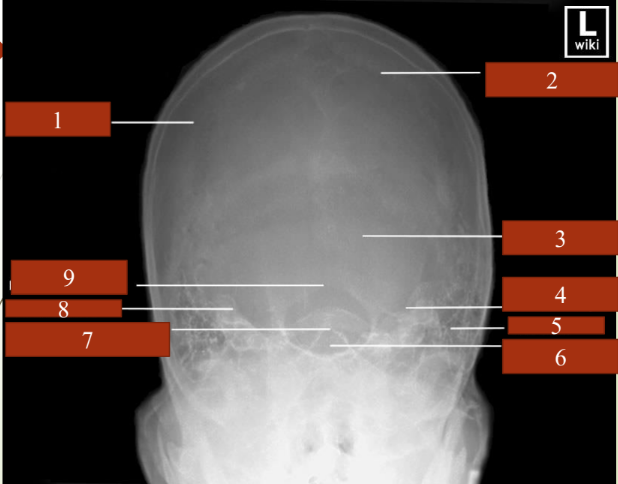

term image

knowt flashcard image